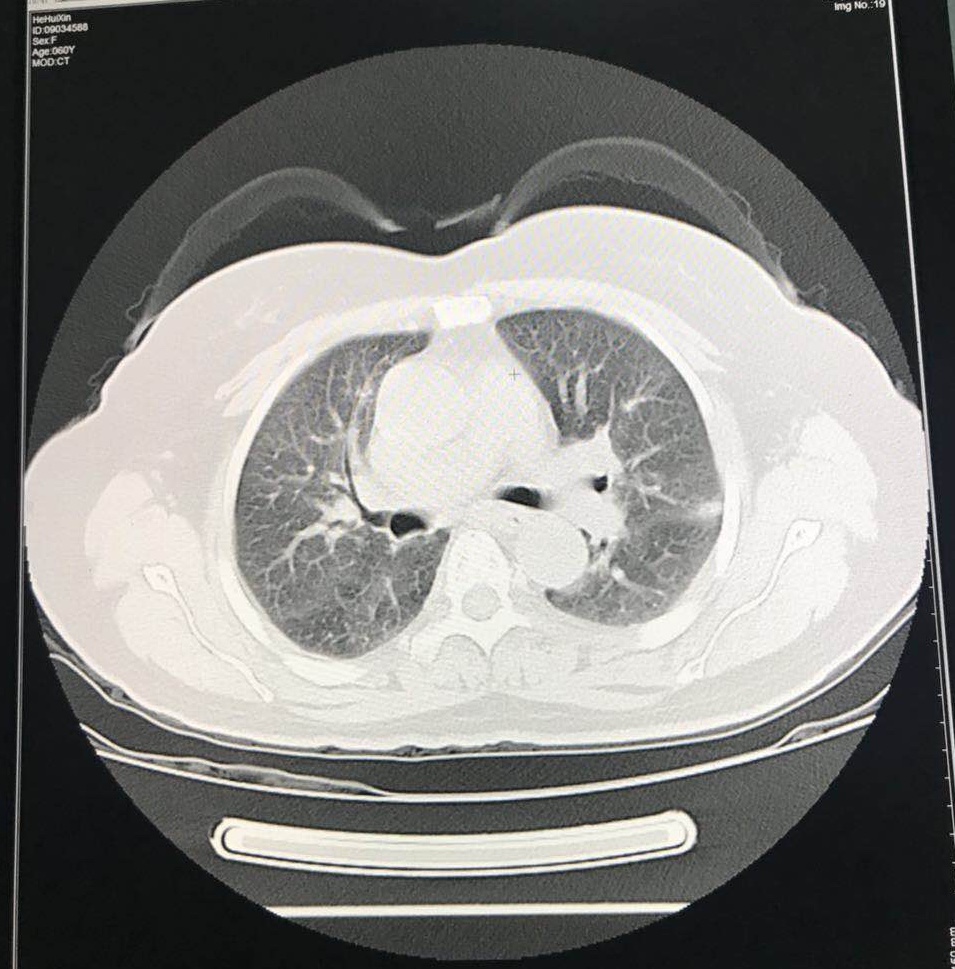

CT:两侧盆腔髂总动脉旁、腹主动脉胖淋巴结多发肿大,较前增大增多,约3.6×2.0cm;左锁骨上、纵膈、右肺门多发肿大淋巴结,最大1.5×1.4cm,较前增大。

两肺多发转移瘤,较前增大增多,最大2.8×2.1cm。

2018-7-5 CT:两侧盆腔髂总动脉旁、腹主动脉旁、左锁骨上、纵膈、右肺门多发肿大淋巴结肿大,较前变化不明显。

两肺多发转移瘤,部分较前增大,部分较前缩小。